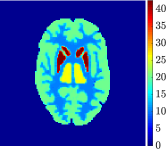

The 3D Hoffman brain phantom is composed of 250 slices, covering the entire head, consisting in black/white images of size . We reduced the image size to to resemble typical PET acquisitions, preserving the shape and features of the original phantom. For sake of simplicity, we selected a middle slice including eight anatomical structures that can be subdivided into the four homogeneous functional regions in Figure 2(a): grey matter (region 1), white matter (region 2), basal ganglia (region 3), and thalamus (region 4). Then, for each region, we assigned a ground-truth set of rate constants of the two-compartment model for FDG kinetics (described in Section 2) and a specific blood volume fraction . The numerical values of such parameters, as reported in Table 1, have been chosen in order to reproduce a realistic framework for the FDG uptake of a human brain [20, 21, 44, 45]. The ground-truth parametric images are shown in Figure 3.

Figure 4, Figure 5, and Figure 6 show the mean images computed over the ten reconstructions obtained by the methods reg-AS-TR, reg-GN, and by the Matlab routine lsqcurvefit implementing a standard Trust-Region-Reflective least-squares algorithm [11, 10]. We used the noise-free IF and the perturbed IF with and of noise, respectively. Figure 7 contains mean and standard deviation values of the kinetic parameters computed over the ten reconstructions and over each one of the four homogeneous regions, for each one of the three noise levels on the IF.

In general, reg-AS-TR and lsqcurvefit seem to provide similar mean reconstructions, although uncertainties associated to lsqcurvefit are significantly bigger. On the other hand reg-GN seems to systematically underestimate the parameter values within region . Furthermore and as expected, for all methods the quality of the parametric reconstructions deteriorates with increasing noise levels; this is more clear from the and parametric images, probably due to the different sensitivities of the data with respect to the model parameters [37]. In reg-GN and lsqcurvefit some artifacts can be observed at the edges of the homogeneous regions, especially around region and region , whereas the effect of regularization in reg-AS-TR results in a reduced presence of artifacts while the structure of the regions is preserved. This general trend is confirmed by the error-bar plots of Figure 7. Finally, the frames in Figure 8 corresponding to reg-AS-TR show a significant improvement of the image quality with respect to what is provided by the other two approaches.